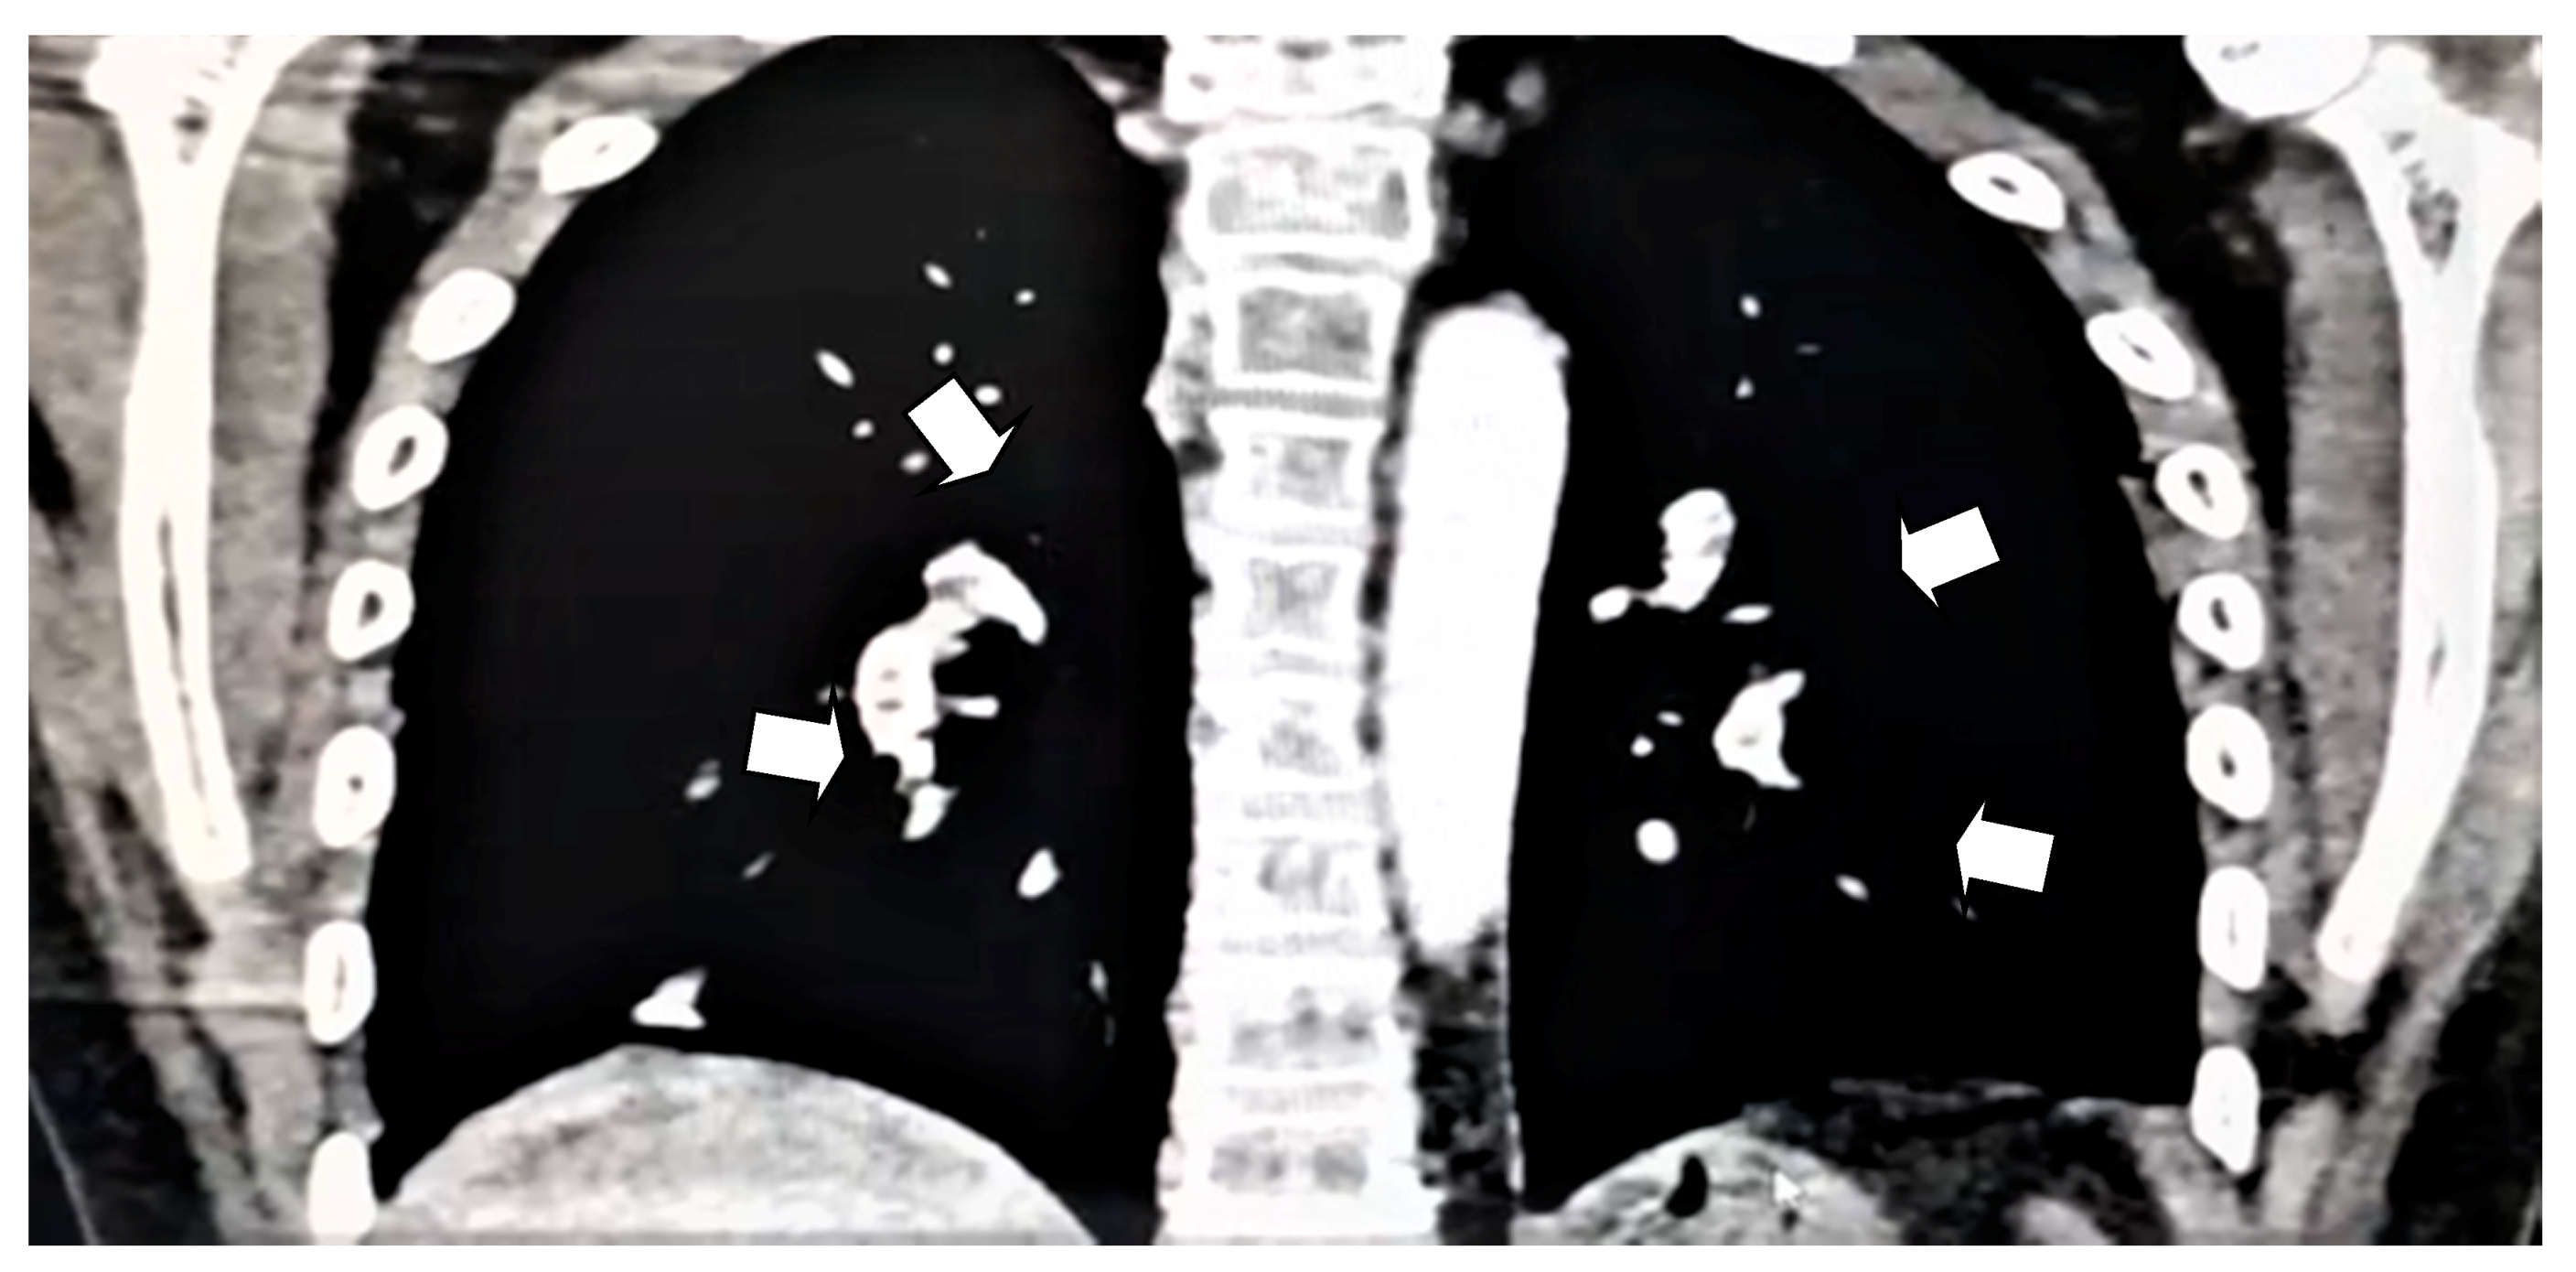

Bilateral Pulmonary Embolism in a 12-Year-Old Girl with Steroid-Resistant Nephrotic Syndrome

2. Case Presentation